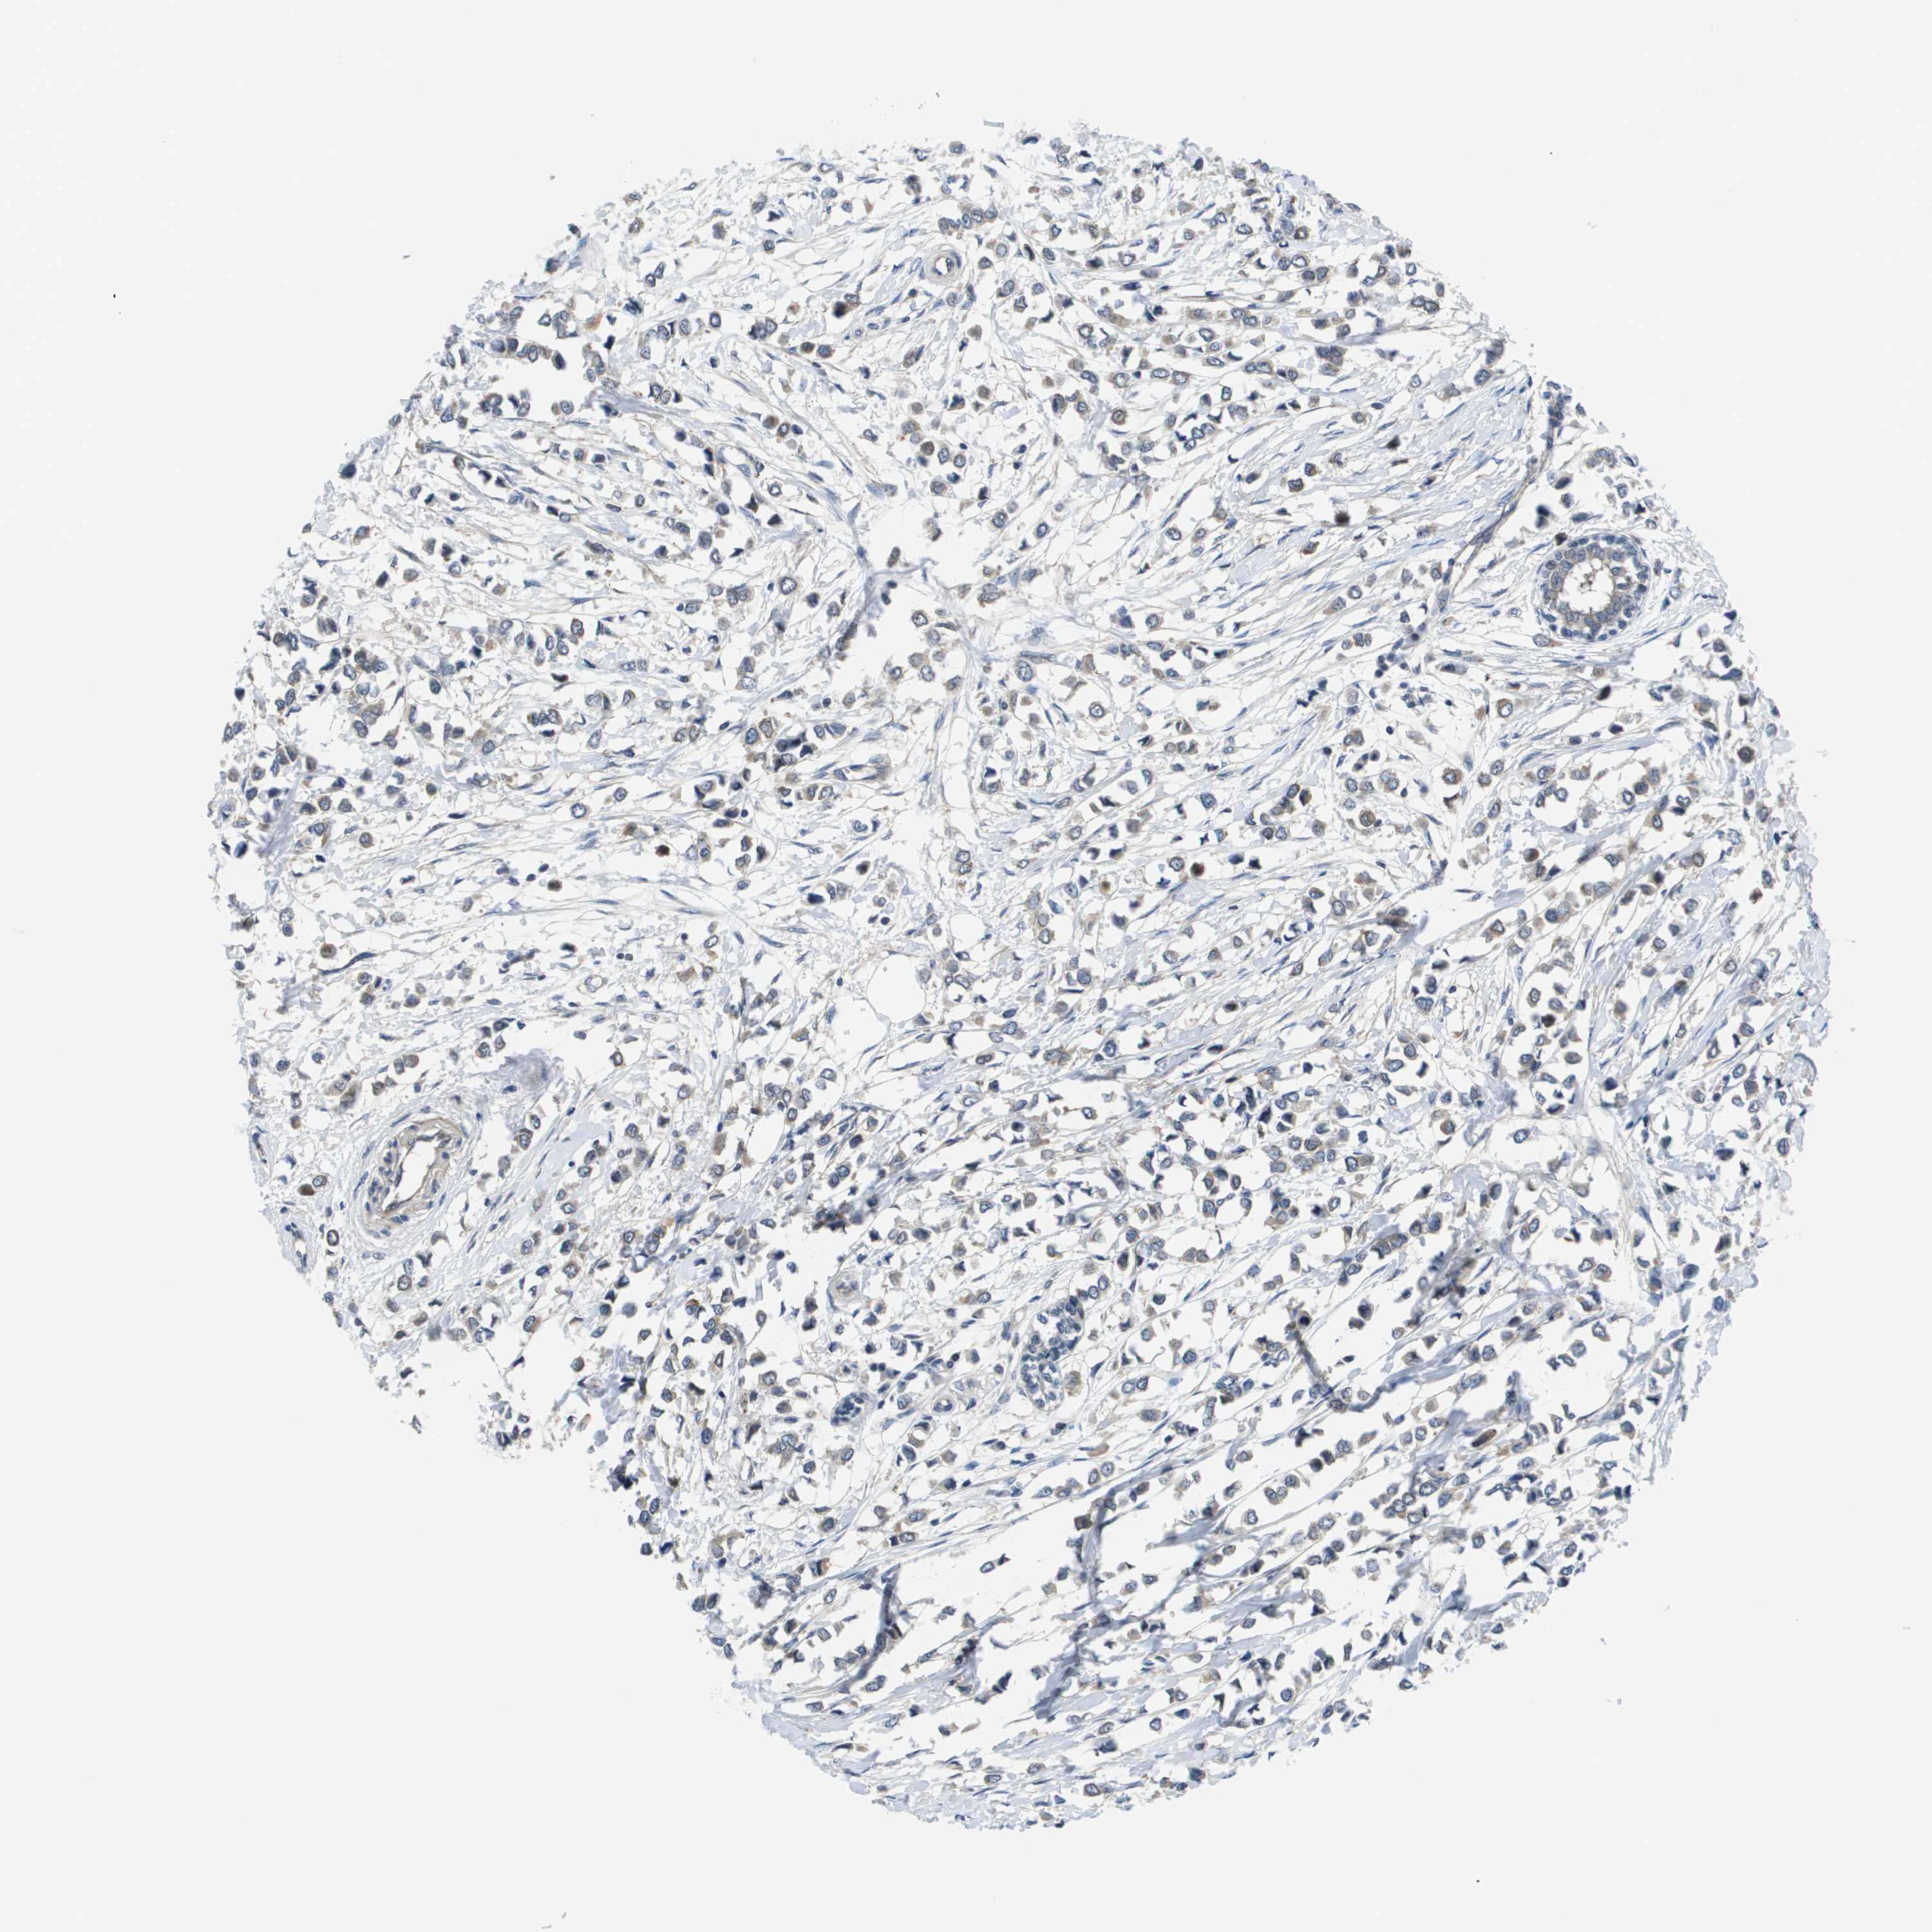

CANCER BREAST CANCER Show tissue menu

BRCA TCGA BRCA VALIDATION PROTEIN EXPRESSION